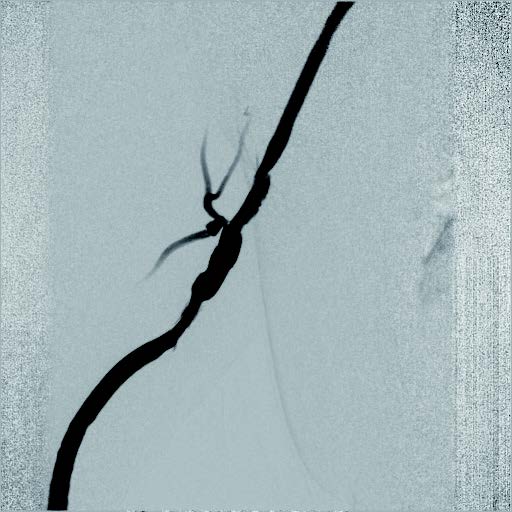

実際の治療

静脈とはいえ、透析患者においては硬化性変化が強い病変が多く、indentation を残さずに pre dilatation をかけておくことが重要と考えられる。そこで、径7 mmのバイアバーン® ステントグラフト留置前に、径6 mmの高耐圧バルーンにてしっかり拡張し、indentationを残さないことを確認した。バイアバーン® ステントグラフト留置後もバルーンでステント内、特に人工血管とのオーバーラップ部位にしっかり圧をかけて後拡張を行っている。

術後経過

半年以上経過フォローしているが、本稿の執筆時点では、人工血管および、バイアバーン® ステントグラフト内に再狭窄が認められず、順調に経過している。同肢には感染徴候も認めていない。